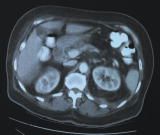

The patient's antibiotic regimen was changed to IV ciprofloxacin, 500 mg every 12 hours. She became afebrile, and her pain was considerably relieved within 48 hours. Her diabetes was well controlled, and she was discharged with the draining catheter in place. She was evaluated 1 week later in the outpatient clinic. The catheter was removed after a CT scan showed complete resolution of the perinephric abscess (Figure). She was advised to continue the oral ciprofloxacin for another week.